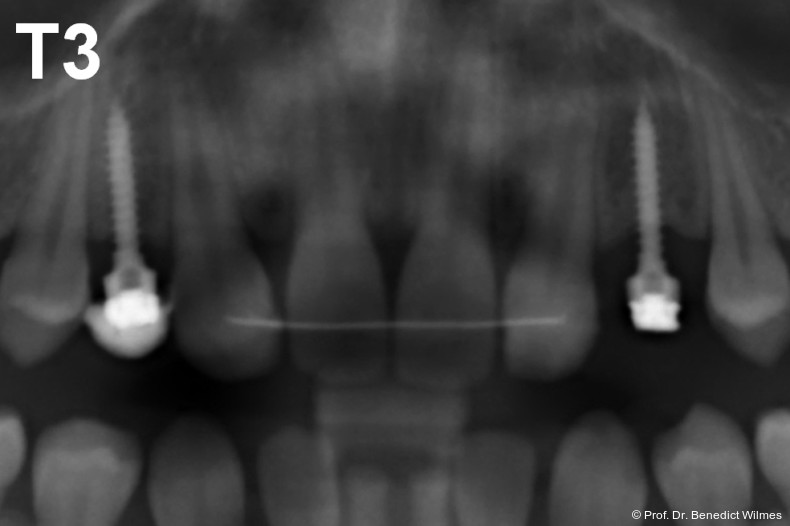

Ein 14-jähriger Patient wurde bei Aplasie der beiden oberen seitlichen Schneidezähne mit dem Ziel der beidseitigen Lückenöffnung kieferorthopädisch therapiert (Abb. 1a+b). Zum Ende der kieferorthopädischen Behandlung wurden zwei Miniimplantate in Regio 2er als temporärer Zahnersatz inseriert (Benefit System, PSM, 2 x 13 mm, Abb. 2a+b). Nach Abdrucknahme wurden Kronen auf den Peek-Abutments modelliert und diese mit Kunststoff auf die Abutments geklebt (Abb. 3a–d). In den Abbildungen 3 und 4 sind die klinischen und röntgenologischen Nachkontrollen innerhalb der nächsten achteinhalb Jahre dokumentiert. Man erkennt einen sowohl in der Höhe als auch in bukkopalatinalen Breite verbleibenden gesunden Knochen ohne Anzeichen einer Atrophie. Im Alter von 23 Jahren wurden die definitiven Implantate ohne die Notwendigkeit einer Augmentation eingesetzt (Abb. 5) und nach Einheilung prothetisch versorgt (Abb. 6a–e und Abb. 7a–c).

Nach Abschluss der kieferorthopädischen Pfeilerverteilung wurden zwei Miniimplantate in Regio 3er inseriert (2 x 13 mm). Nach Herstellung im Labor wurden Kronen auf den Miniimplantaten aufgeschraubt (Abb. 13+16a–d). Auch hier wurde darauf geachtet, dass die Kronen aus der Okklusion geschliffen wurden (Abb. 14). Bei den Nachkontrollen zeigten sich ebenfalls stabile Miniimplantate und ein entzündungsfreies Implantatlager ohne erkennbare Atrophie des Knochens (Abb. 15 und 16a–d).